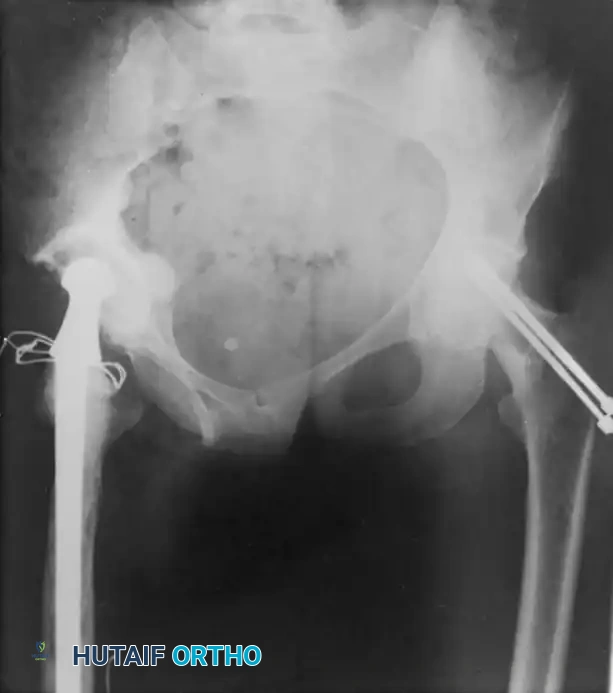

Associated Surgical & Radiographic Imaging